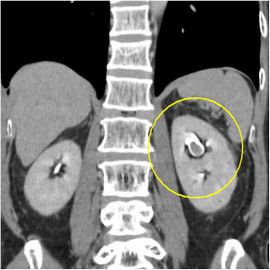

[腎盂がん(左)] 手術:左腎尿管全摘術

CT画像